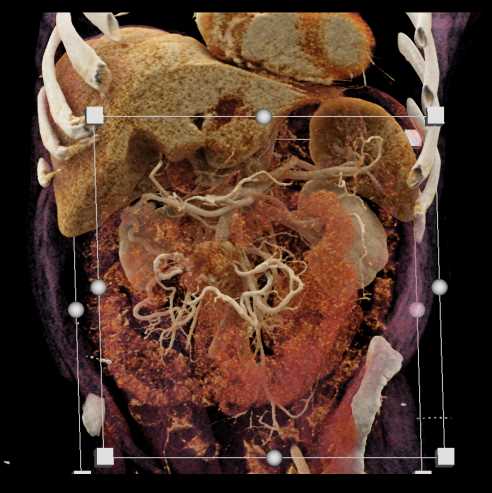

Carcinoid Tumor with Desmoplastic Reaction